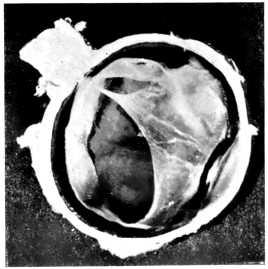

PLATE V.

28.

INJURIES TO UVEAL TRACT

curly bracket span

54

29.

FOREIGN BODY (TIP OF COPPER PROBE) IMBEDDED IN THE EYE

30.

TRAUMATIC DETACHMENT OF RETINA AND CHOROID

31.

WHOLE-SECTION OF FIG. 19

32.

PART OF THE ABOVE MAGNIFIED TO SHOW LENS IMBEDDED IN INFLAMMATORY EXUDATE

33.

PHAGOCYTOSIS